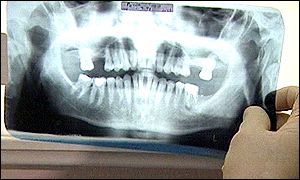

Ms Edwards had a broken tooth

When she was eventually seen by the dentist, Ms Edwards had to have her broken tooth filed and have a crown fitted.